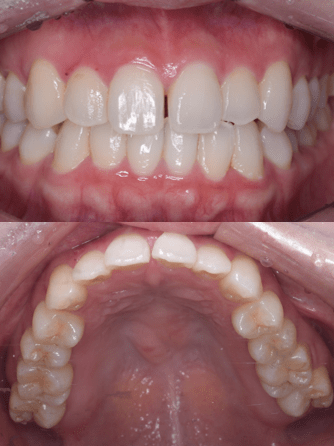

症例写真(治療後)

治療後:

矯正治療と虫歯の治療すべて終わったときの写真になります。見た目も最初の頃とは全く違いますし、お口の中もすごく綺麗です。